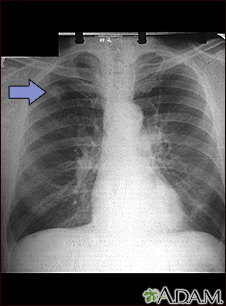

Adenocarcinoma - chest x-rayBackAdenocarcinoma - chest x-rayThis chest x-ray shows adenocarcinoma of the lung. There is a rounded light spot in the right upper lung (left side of the picture) at the level of the second rib. The light spot has irregular and poorly defined borders and is not uniform in density. Diseases that may cause this type of x-ray result would be tuberculous or fungal granuloma, and malignant or benign tumors. E-mail FormEmail ResultsName:Email address:Recipients Name:Recipients address:Message: